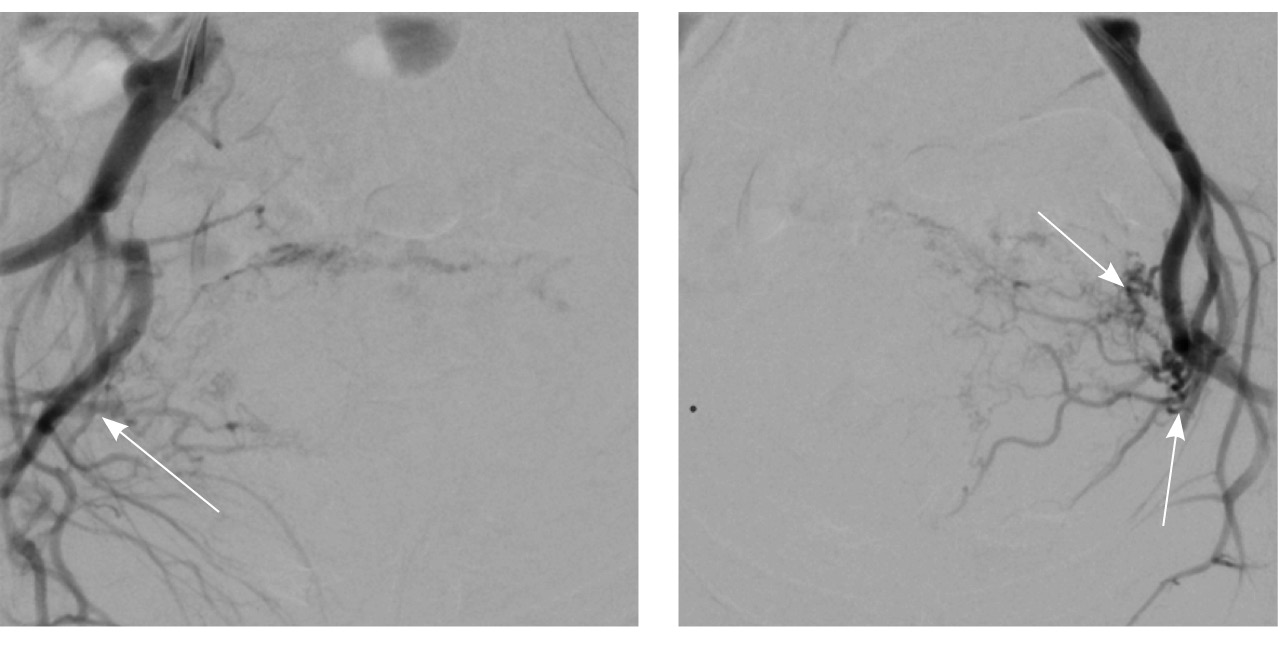

По наружной поверхности нижнего маточного сегмента и в параметрии определяется наличие полнокровной сосудистой сети с артериовенозными анастомозами. При контрастировании визуализируются фрагментарные участки гиперваскулярного накопления контраста вышеописанным образованием в рубцовой нише, а также определяется наличие артериовенозной сосудистой мальформации (рис. 2).

Рис. 2. Магнитно-резонансная томограмма, динамическое контрастное усиление в режиме Т1-взвешенного изображения FS. До контраста (А), в раннюю артериальную фазу (Б), паренхиматозную фазу (В), выделительную фазу (Г) определяются многочисленные патологические сосуды, зоны неоангиогенеза, сосудистые шунты как в стенке матки, так и в параметрии по типу артериовенозной мальформации